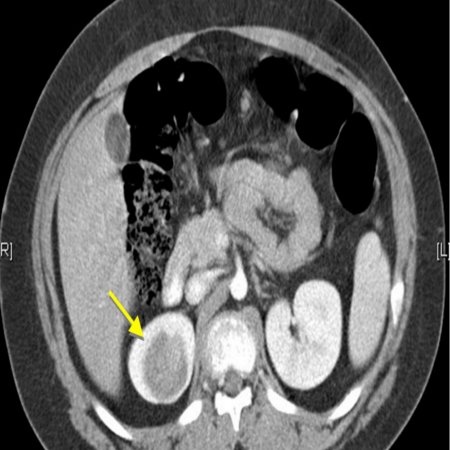

Рисунок 2. КТ: опухоль при поступлении. Клинически: при пальпации опухоль в проекции правой почки до 12 см в диаметре. Общеклинические исследования в пределах возрастной нормы. При КТ органов брюшной и грудной полости: КТ-картина объемного образования правой почки без признаков интрапульмональных метастазов (см. рис. 2). УЗИ брюшной полости: в проекции правой почки солидно-кистозное образование 101ґ114ґ99 мм, объемом 500 мл, васкуляризация активная, интактная часть почки 57ґ12ґ40 мм. Объемное образование правой почки — опухоль Вильмса. Предварительный диагноз: опухоль Вильмса правой почки, 2-я стадия.

Рисунок 3. Контрольная КТ: опухоль после предоперационной химиотерапии. Ребенку проведена предоперационная химиотерапия. На 5-й неделе лечения КТ-контроль показал уменьшение опухоли в размерах до 90ґ80ґ100 мм (см. рис. 3).